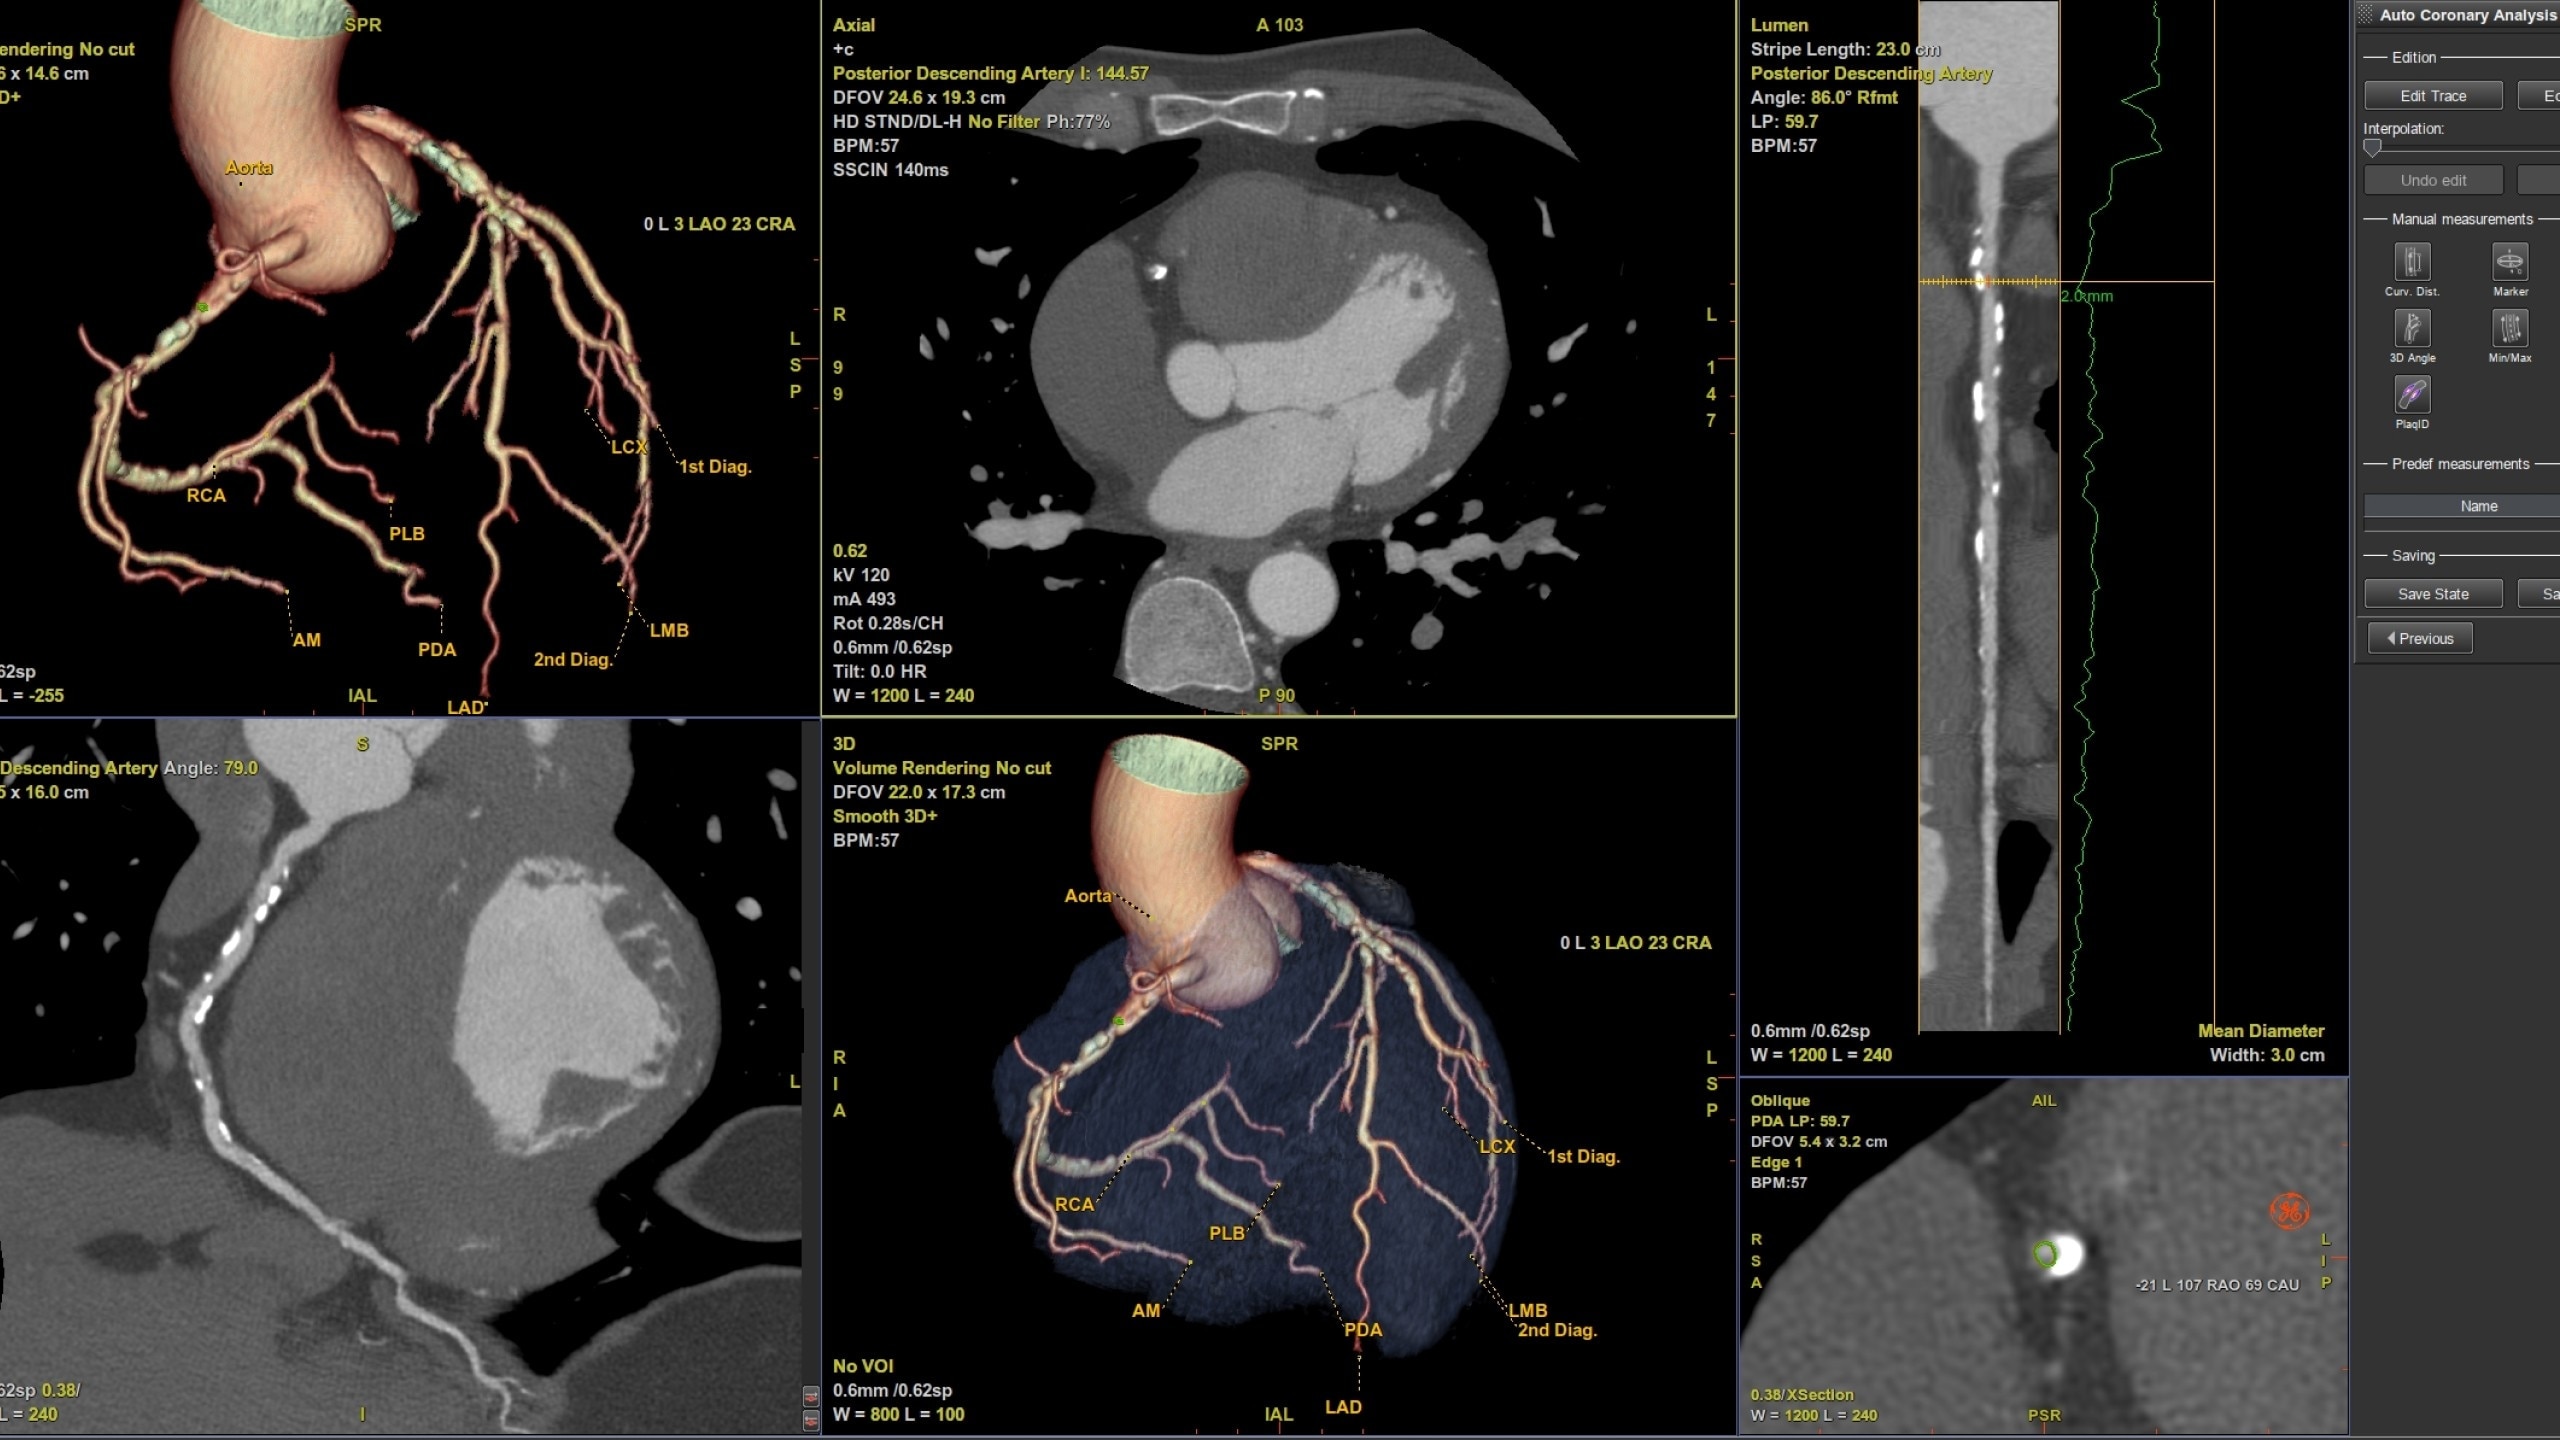

CardIQ Xpress 2.0 Reveal

Bringing integration and automation

to your CT Cardiac post processing needs

Automation

Automatically segments the coronary tree, tracks and labels the coronary arteries

• Pre-processing automatically recognizes cardiac

datasets and performs all segmentations as data

arrives on the system saving processing time

• Auto Coronary analysis automatically segments the

coronary tree, tracks and labels the coronary arteries

• Three pre-defined orientation protocols for easy review

of the coronary vessels and chambers